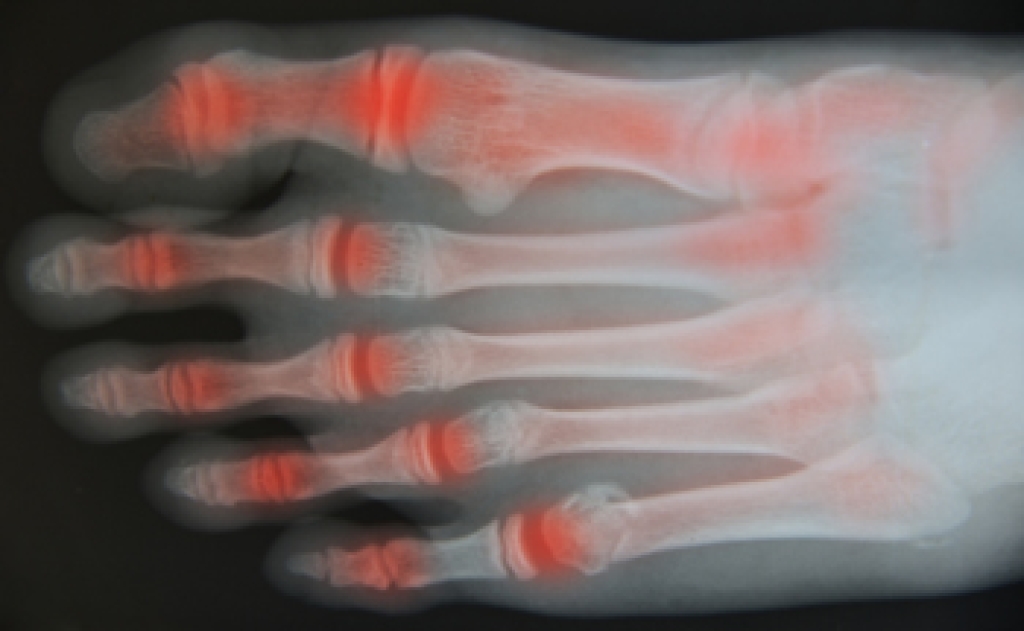

In order to diagnose your bunion, your podiatrist may ask about your medical history, symptoms, and general health. Your doctor might also order an x-ray to take a closer look at your feet. Nonsurgical treatment options include orthotics, padding, icing, changes in footwear, and medication. If nonsurgical treatments don’t alleviate your bunion pain, surgery may be necessary.